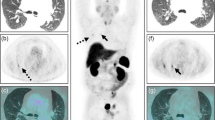

In all cases (except subject 26 for one neuroradiologist), adenomas detected on baseline PET images were also detected upon oCRH stimulation as well. Importantly, both neuroradiologists reported an increase in 18F-FDG-PET detection of adenomas following CRH administration (Fig. 3). NP correctly detected the adenoma on 8/27 baseline PET scans and in 6 additional cases (14/27) with oCRH stimulation. JS correctly detected the adenoma in 12/27 baseline scans and in 3 additional cases (15/27) with CRH stimulation. There was no statistically significant increase in detection of adenomas by either neuroradiologists by introducing a delay in PET imaging following CRH administration (Chi Square for trend, NP: p = 0.05; JS: p = 0.66,) (Table 2). Readings from Subject 26 were diametrically opposite and conflicting, and therefore excluded from further analysis (Table 1). Interestingly, in two cases, adenomas initially read as MRI negative were detected on PET imaging by both neuroradiologists (Subjects 10 and 14). In Subject 10, the adenoma was only detected following administration of oCRH (Table 1 and Fig. 3).

MRI Negative adenomas are detected with baseline and CRH stimulated FDG-PET imaging. In five subjects (including Subjects 14 and 10), MRI of the pituitary gland was negative (a and d). In Subject 14, a histopathologically confirmed adenoma was visible (white arrowhead) on baseline b and CRH stimulated FDG-PET imaging c. In Subject 10, baseline FDG-PET imaging e failed to demonstrate an adenoma. A distinct adenoma within the left cavernous sinus was visible (white arrowhead) upon CRH stimulated FDG-PET imaging f

Ultimately, the role of FDG-PET imaging in CD would likely be as a complementary imaging modality. In this study, we found that in two of the five tumors read as negative on clinical MRI scans, adenomas were detected on PET imaging. In one of these instances, the adenoma was detected only after oCRH stimulation, suggesting a complementary role for FDG-PET imaging following secretagogue stimulation in MRI negative cases of CD. The size of adenomas (on MRI of the pituitary gland) does not appear to be associated with increased detection on FDG-PET imaging. A valuable property of 18F-FDG-PET in our study was the absence of false positive reads. In actual clinical practice, in many instances, MRI findings of adenomas are uncertain. We believe that in such instances, oCRH-stimulated 18F-FDG-PET imaging may help clinicians localize the adenoma pre-surgically.